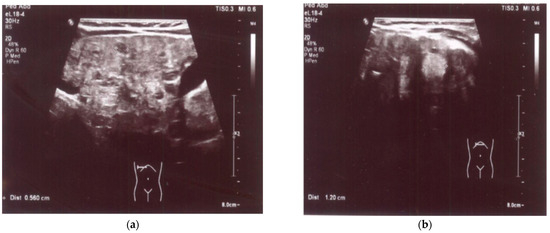

An enlarged liver (cranio-caudal dimension about 9.5–10 cm) with an irregular contour and diffusely heterogeneous parenchyma was observed both in ultrasound and in abdominal computed tomography (CT) imaging studies. Multiple smaller hypoechoic lesions were noted on abdominal ultrasonography (US) (Figure 1a,b), while hypodense lesions up to ~0.5 cm in size, with a larger lesion in the left lobe up to 1.2–1.6 cm in size, were also observed at the same locations on abdominal CT. Additionally, the spleen was enlarged and homogenous, measuring about 10 cm by 4 cm in size. A liver biopsy revealed signs of cirrhosis with steatosis. No evidence of neoplastic changes was found.

Figure 1.

(a) US: liver with multiple smaller hypoechoic lesions. (b) US: hypoechoic lesion up to 1.2 cm in size in the left hepatic lobe.